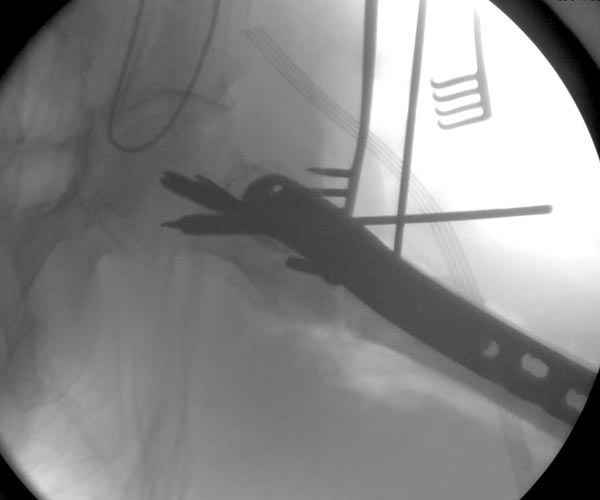

При отсутствии КТ, снимок на вытяжении поможет увидеть общую картину расположения отломков, особенно потенциальные места введения импланта. Риск раскола в этом случае огромный, поэтому больной должен быть дообследован.

Здесь пара похожих случаев.

Увожаемый коллега,мое мнение:фиксация и\медул.блок. стержнем Gamma-long "STRYKER". Вероятно, закрыто сделать полностью может не получится. Откроетесь на 6-8 см. для репозиции промежуточного фрагмента, но только после установки стержня. Удачи!!!